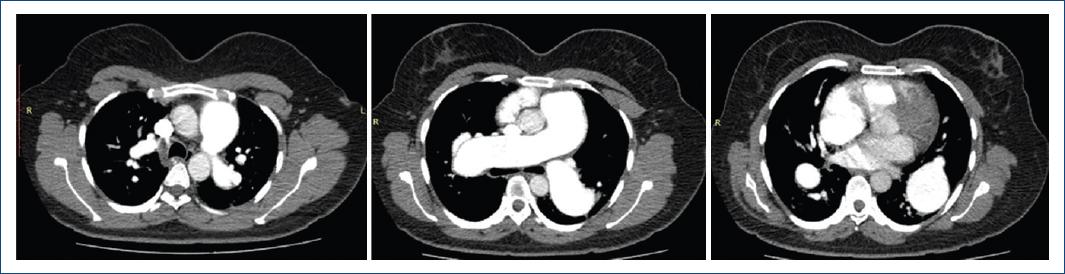

We present the case of a 35-year-old patient with neurological maturation retardation and a history of bicuspid aortic valve and subaortic membrane, who had started 15 days earlier with progressive dyspnea of functional class II to III-IV, orthopnea and angina in the last 24 hours. She had edema in the lower limbs, crackles in the lung bases, first and second tones present, and a tricuspid systolic murmur of 3/6 intensity with Rivero Carvallo's sign. The chest X-ray revealed cardiomegaly and dilatation of the pulmonary artery (Figure 1). Transthoracic echocardiography showed a preserved ejection fraction, systolic flattening of the interventricular septum, slightly dilated right ventricle with a 19 mm TAPSE, bicuspid aortic valve with preserved opening, with a small subaortic membrane, pulmonary, tricuspid, mitral and mild aortic aortic insufficiencies, PSAP 67mmHg, without intracardiac shunts. Acute pulmonary embolism was excluded by pulmonary angiography. The tomography showed a dilation of all the branches of the pulmonary artery (Figures 2 and 3). The right heart catheterization showed a mean pulmonary pressure (PAPm) of 52 mmHg, pulmonary capillary pressure (PCP) 13mmHg, pulmonary vascular resistance (PVR) 6 wood units, and cardiac index of 3.53 liters/minute/m2. Diuretic treatment with furosemide generated clinical improvement. Sildenafil and bosentan were subsequently started.

Figure 2 Three axial slices at three different levels of a pulmonary angiography. 48mm pulmonary artery trunk, AP/Ao ratio: 1.7, dilation of the interlobar pulmonary arteries.

This case is classified as a severe pulmonary hypertension precapillary phenotype of group 1.4.4 associated with congenital heart disease. The great dilation of the pulmonary artery and its branches led us to present chest radiography and pulmonary angiography images.